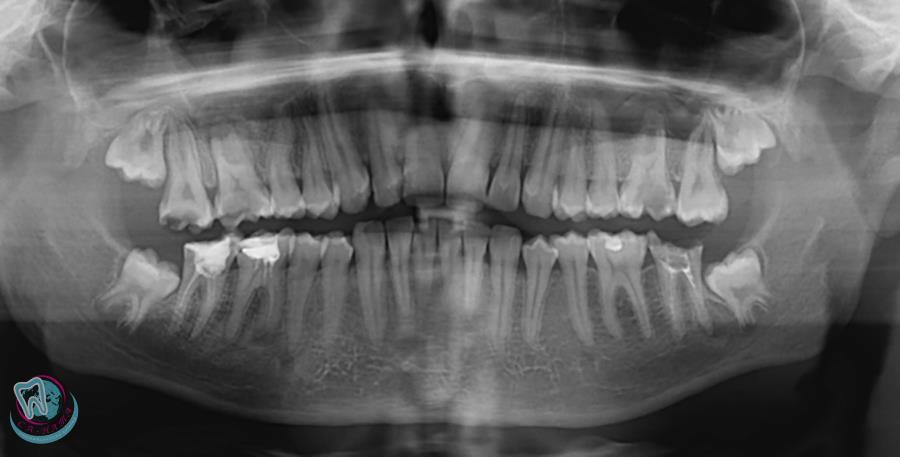

Дентальные снимки и диагностика кариеса